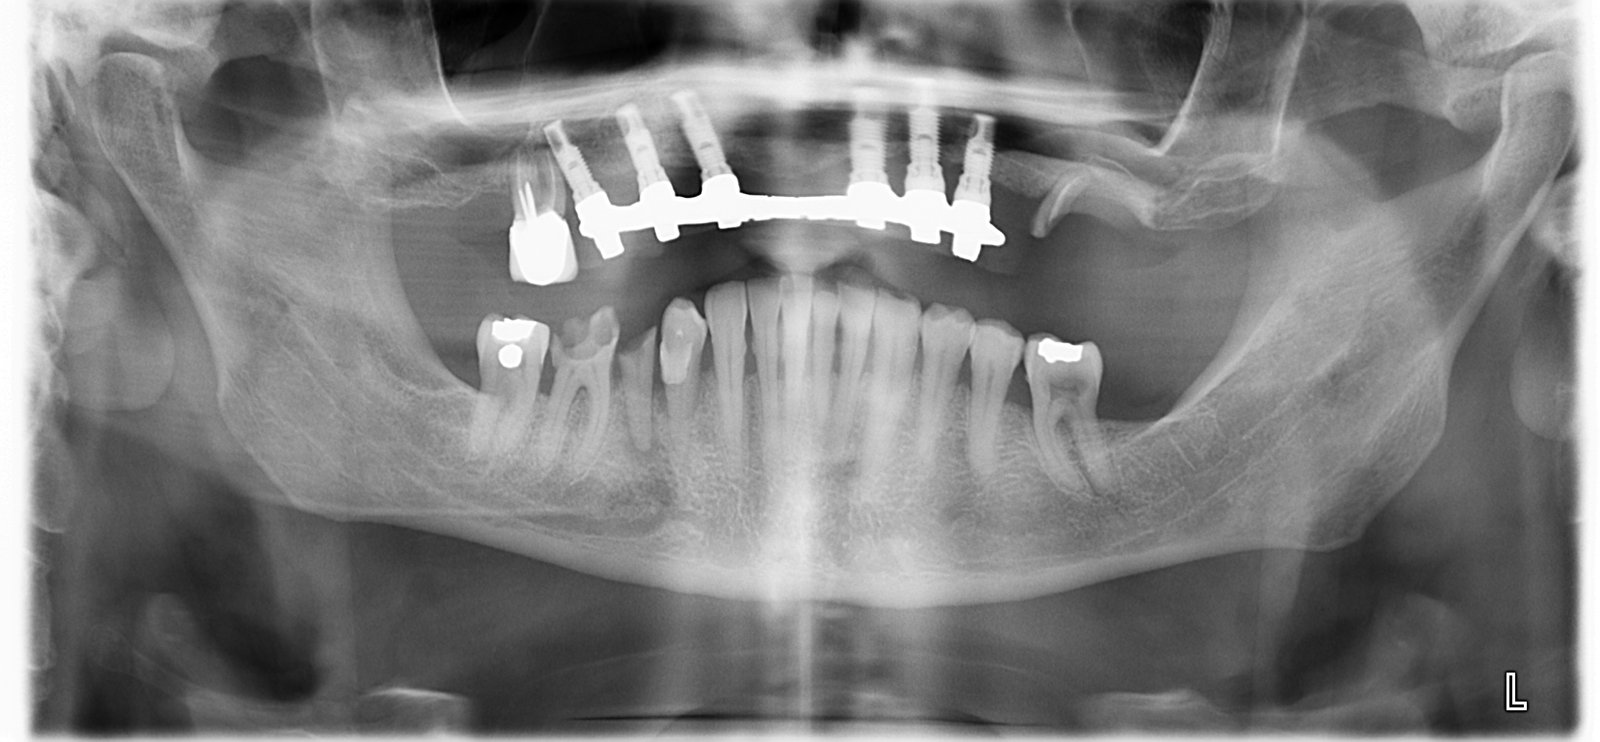

Paciente de 60 años, se colocó implantes hace 20 años, acude a nuestra consulta para cambiar prótesis híbrida. Necesito saber que implantes lleva creemos que son de conexión interna. Además [...]

Según la paciente fue colocado hace unos 15 años, sabéis que implante es??

Buenas tardes. Me gustaría saber si me pueden ayudar a saber cuales son los implantes que tiene mi paciente, para así poder comprar los aditamentos. Muchas gracias de antemano por [...]